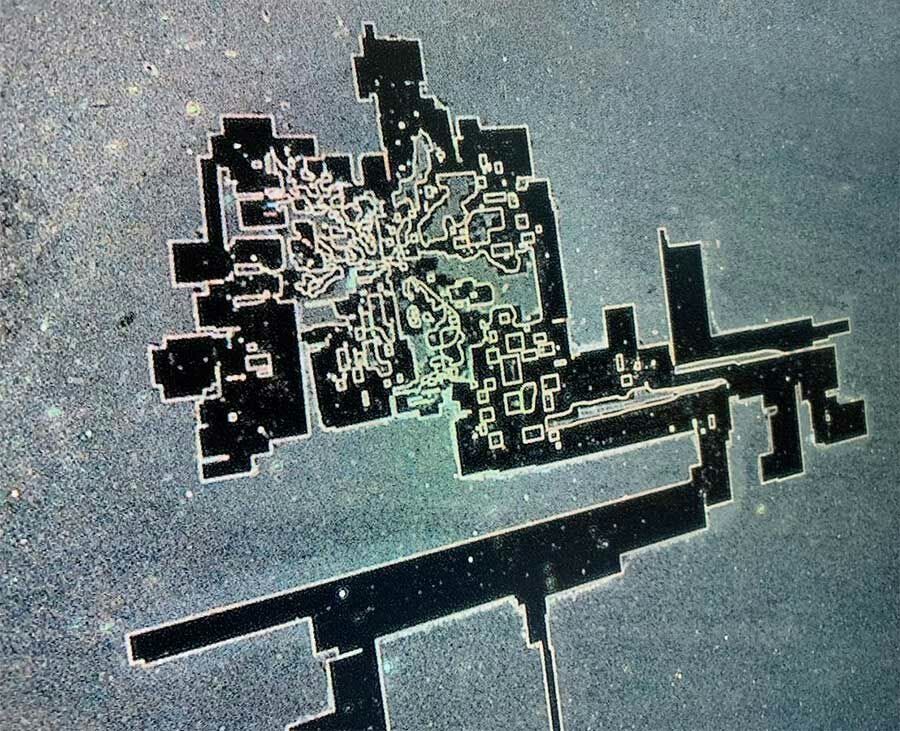

Generalmente solo después de la desecación de estas muestras o por calor pudieron observar algo verdaderamente terrorifico descrito como circuitería o algun tipo de bionanotecnología o nanotecnología que ensambla.

Este estudio recientemente publicado en Italia confirma una vez más las nanoestructuras de autoensamblaje en la sangre de personas inyectadas con C19. Los autores correlacionan los hallazgos de sangre con los síntomas del afectado. Por ejemplo, se discutió este caso:

The authors show that these self-assembly nanoparticles conglomerate to create massive structures. These provide the basis for extensive clotting and abnormal blood flow.

Here are further self assembly nanostructures:

The sudden transition, usually at the time of a second mRNA injection, from a state of perfect normalcy to a pathological one, with accompanying hemolysis, visible packing and stacking of red blood cells in conjunction with the formation of gigantic conglomerate foreign structures, some of them appearing as graphene-family super-structures, is unprecedented.

Estas 4 imágenes ilustran la variedad de fenómenos y objetos inusuales encontrados en la sangre de sujetos vacunados con Comirnaty BioNTech/Pfizer (Cortesía de Helen Krenn)MÁS

These substances, furthermore, “are visible under the dark-field microscope as distinctive and complex structures of different sizes, can only partially be explained as a result of crystallization or decomposition processes, [and] cannot be explained as contamination from the manufacturing process,” the researchers found.